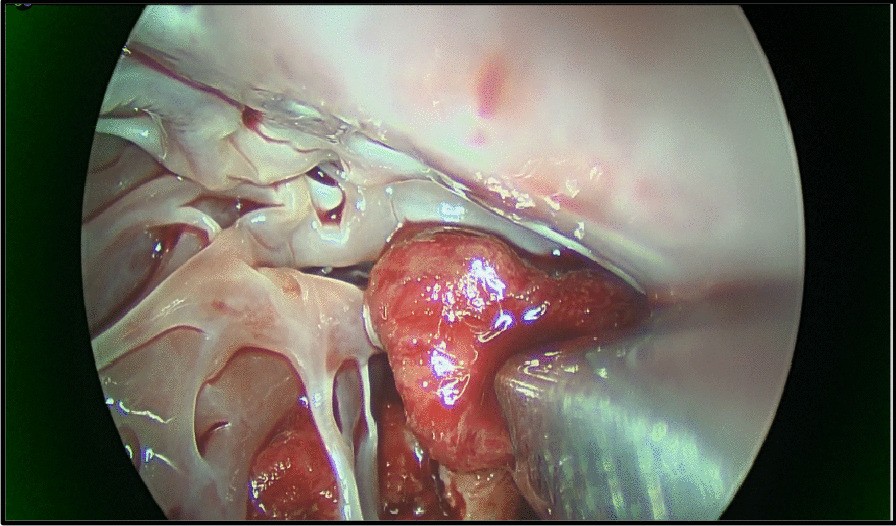

Fig. 3From: Video assisted, transaortic removal of left ventricular thrombus during concurrent cardiac surgery: a case reportSingle shafted instrument removing thrombusBack to article page